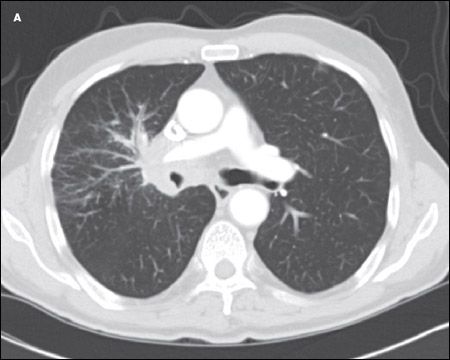

A CT scan of the chest showed an amorphous soft tissue mass that encased and constricted the right main pulmonary artery and the right main stem bronchus (A). Extensive round masses were visible in the liver; the largest mass was in the right medial hepatic lobe and measured 2.7 × 2.4 cm (B).

SCLC typically presents as a large central mass (as in this patient) with mediastinal adenopathy. SCLC can infiltrate the submucosa, causing either intrinsic or extrinsic compression of the bronchi. SCLC has a propensity for spreading to the liver, brain, bone, and bone marrow. The neutropenia and thrombocytopenia seen in this man can be explained by the infiltration of his bone marrow by the SCLC. In a series of 129 patients with SCLC, 30% had bone marrow involvement. However, in only 2.3% was the bone marrow the only site of metastatic disease.7 Other presenting symptoms include cough, dyspnea, hemoptysis, chest pain, postobstructive pneumonia, and the paraneoplastic syndromes mentioned above.